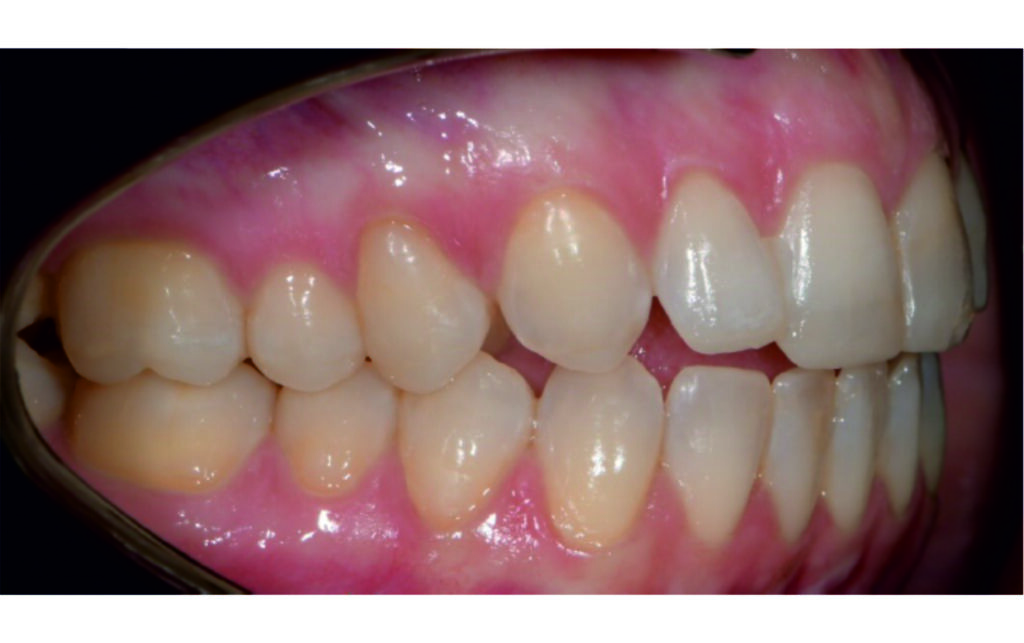

Angle Class II 2mm on the right, Angle Class II 2mm on the left, light mandibular asymmetry to the right, lower central line 1mm to the right, upper central line 1,5mm to the left, 1mm overjet and overbite. Sagittal asymmetry of upper dental arch. Light crowding upper and lower frontal segments, severe attrition of posterior teeth, night bruxism. Normal sagittal position of both jaws, high angle case, steep mandibular ramus,excessive lower facial height, open bite tendency.

The case initially presented as a moderate Class II on the right and a Class II tendency on the left, with tapered dental arches and an anterior open bite extending to tooth 26 in segment II.

In segment I, the open bite reached up to the first premolar.

A 1.5 mm deviation of the upper dental midline to the patient’s left was noted, along with a slight mandibular midline shift to the right, likely due to asymmetrical mandibular growth observed in the facial structure. Severe mesial rotations of teeth 16 and 26 were evident in the initial records. As derotation of 16, 26, 17, and 27 progressed up to aligner 16, the premolars in segments I and II moved distally, resulting in a bilateral Class I relationship, as intended in the initial treatment plan.